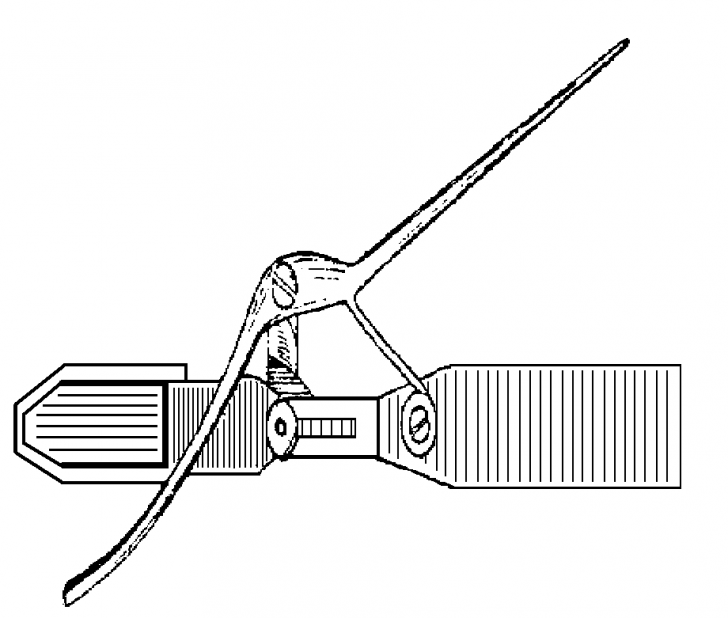

PARTE SPECIALA LITIAZA BILIARA

PARTE SPECIALA LITIAZA BILIARA - MOTIVATIA LUCRARII - Litiaza biliara este cea mai frecventa afectiune a vezicii biliare, ea afecteaza un procent important al populatiei: 10-20% din indivCiteste tot ... 13404 cuvinte

Dimensiune mare

+ cu imagini |